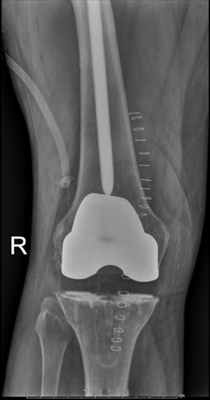

Клинический пример №1.

Правосторонний посттравматический гонартроз Rg III ст. Сросшийся перелом правой бедренной кости в условиях синтеза стержнем.

После тотального цементного эндопротезирования коленного сустава эндопротезом Sigma CR.